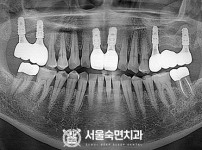

임플란트-전후사진3